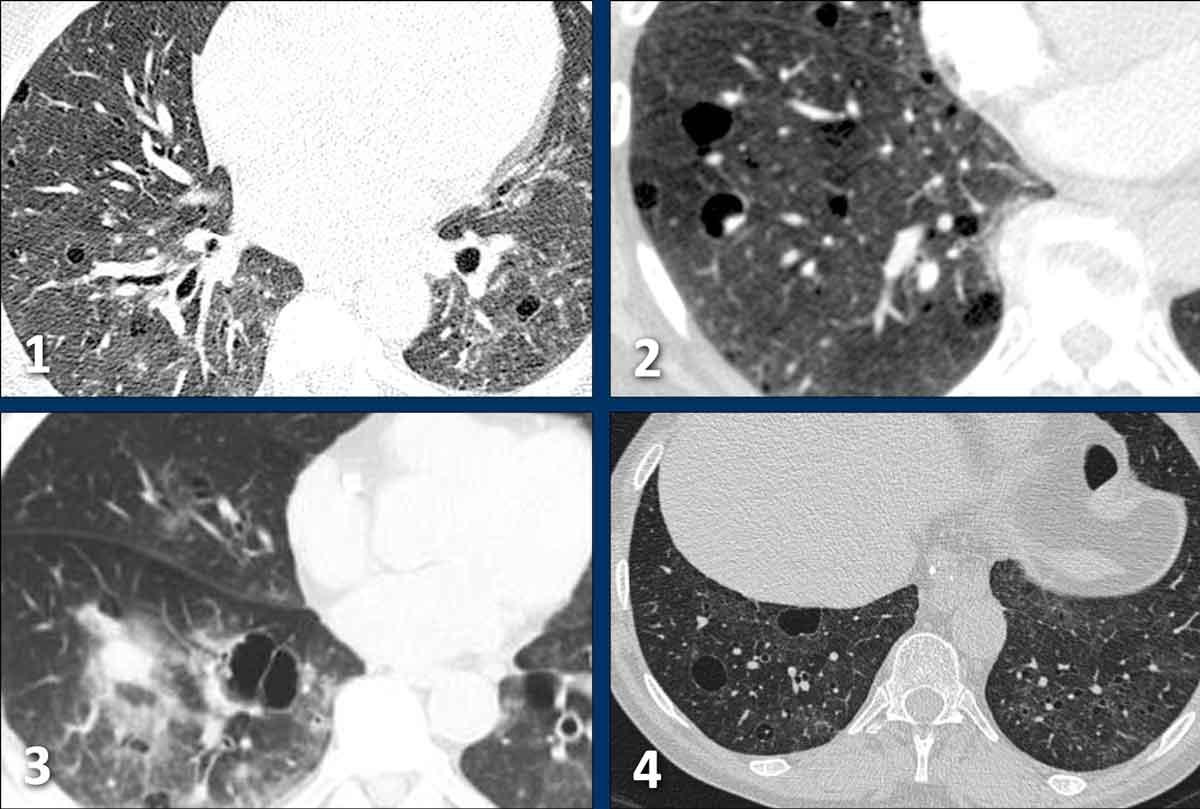

Các nang trong BHD có xu hướng phân bố ưu thế ở vùng phổi thấp và ngoại vi.

Đôi khi các nang có ranh giới được xác định bởi các vách liên tiểu thùy, tạo cho chúng hình dạng tam giác hoặc thấu kính đặc trưng (đầu mũi tên trong hình 2 và 4).

Các nang BHD không nhiều, thường ít hơn 50 nang. Đôi khi số lượng nang rất ít với hình ảnh rất tinh tế (hình 3), nhưng không được bỏ sót.

Việc chẩn đoán xác định là rất quan trọng vì những bệnh nhân này và gia đình của họ cần được tầm soát khối u thận.

Hình ảnh

- Các nang BHD. Một số nang tiếp giáp với màng phổi (mũi tên vàng) hoặc các rãnh liên thùy. Các nang ở vùng phổi thấp cũng có thể gặp trong LIP. Khí phế thũng cạnh vách liên tiểu thùy có phân bố ưu thế ở vùng phổi trên.

- Phân bố ưu thế ở vùng phổi thấp và các nang hình tam giác (đầu mũi tên) trong BHD.

- Lưu ý hình ảnh rất tinh tế với phân bố ưu thế ở vùng phổi thấp.

- Các nang BHD điển hình

Đây là hình ảnh của một phụ nữ 56 tuổi, có tiền sử tràn khí màng phổi tái phát và hiện tại nhập viện lần này cũng vì tràn khí màng phổi (mũi tên).

Hãy phân tích hình ảnh.

Đây là các nang thực sự hay các tổn thương giả nang?

Đây là phát hiện tình cờ hay bạn cho rằng đây là bệnh phổi dạng nang?

Chẩn đoán có khả năng nhất là gì?

Nhận xét hình ảnh

Có nhiều nang thành mỏng – hơn bốn nang. Lưu ý vị trí phân bố gần các rãnh liên thùy và ở ngoại vi phổi.

Kết luận

Đây là trường hợp hội chứng Birt-Hogg-Dubé (BHD).

Bàn luận

Hai bệnh phổi dạng nang thường biểu hiện bằng tràn khí màng phổi là LAM và BHD.

LAM biểu hiện là các nang đơn thuần, thành mỏng, hình tròn hoặc bầu dục, đều đặn với phân bố lan tỏa.

Vị trí ngoại vi và cạnh rãnh liên thùy của các nang BHD thường tạo ra các góc nhọn, khiến chúng có hình dạng thấu kính.

Khi các nang có hình ảnh đặc trưng này, chúng có độ đặc hiệu cực kỳ cao cho chẩn đoán hội chứng Birt-Hogg-Dubé.

Đây là một trường hợp khác của hội chứng Birt-Hogg-Dubé.

Các nang có vị trí điển hình ở ngoại vi phổi gần trung thất (mũi tên đen) và gần rãnh liên thùy (mũi tên trắng).

Đây là một trường hợp minh họa khác với rất ít nang nhỏ ở bệnh nhân mắc hội chứng Birt-Hogg-Dubé.

Đôi khi cần phải quan sát rất kỹ các trường phổi để không bỏ sót các nang và bỏ lỡ chẩn đoán BHD.

Trong trường hợp này, có thể hình dung rằng nếu CT được thực hiện vì lý do khác, người đọc có thể dễ dàng bỏ sót những nang nhỏ này.

Cần nhớ rằng khi phát hiện hơn bốn nang và chúng thực sự là nang, cần phải xử lý các phát hiện này.

Những bệnh nhân này nên được chuyển đến bác sĩ chuyên khoa hô hấp để đánh giá thêm.

Bệnh nhân này được chụp CT để đánh giá khối u thận.

Trong báo cáo chẩn đoán hình ảnh, các nang trong phổi được mô tả là bóng khí (bullae).

Tuy nhiên, các nang này là nang BHD điển hình ở ngoại vi phổi, trong khi bóng khí thường gặp ở bệnh nhân khí phế thũng và có vị trí ở các trường phổi trên.

Đặc biệt khi chỉ thấy một vài nang, hãy nghĩ đến BHD.

Gia đình bệnh nhân cần được tầm soát hội chứng BHD và khối u thận.

Cuối cùng là một trường hợp BHD nặng hơn với các nang kích thước lớn hơn.

Bệnh nhân này nhập viện vì tràn khí màng phổi.

Lưu ý ống dẫn lưu (mũi tên).